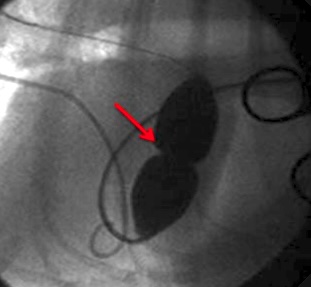

{{/_source.additionalInfo}}Nel cuore di riconosce uno specifico sistema di conduzione deputato a generare e condurre l’impulso elettrico al miocardio di lavoro. Tale sistema si compone di cellule in grado di generare l’impulso elettrico in maniera spontanea e di strutture rappresentate da fasci che propagano lo stimolo agli atri ed ai ventricoli. L’impulso elettric...